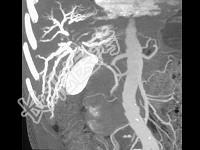

- 单项选择题患者中年,男性, 黄疸,ERCP术后, 三维图像如图,最可能的诊断为 ( )

A、胰腺癌

B、末梢胆管狭窄

C、胆管癌

D、肝门区肝癌

E、十二指肠癌